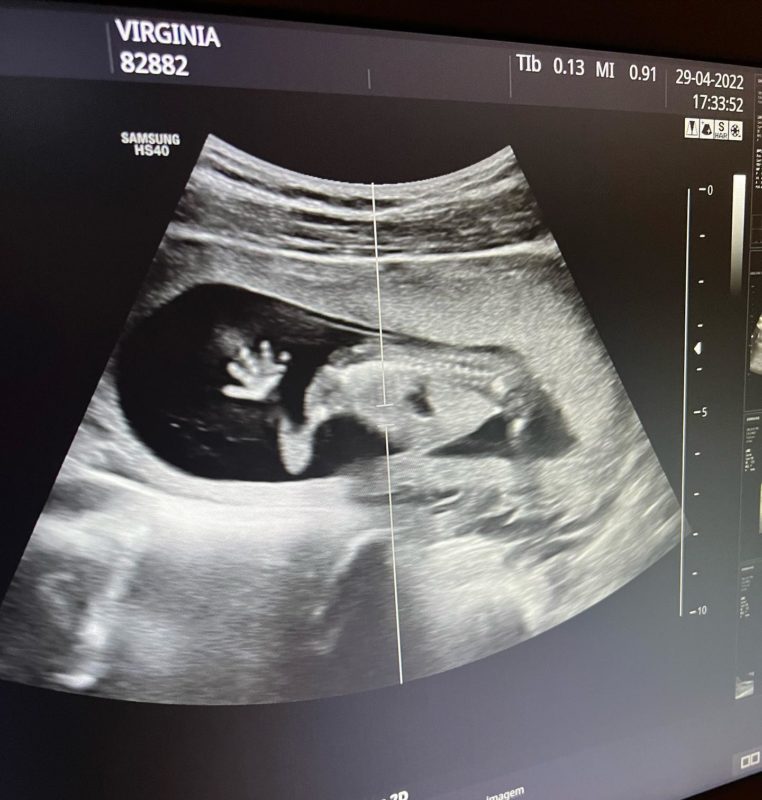

A imagem mostra a mãozinha e o pezinho do bebê, o que encantou os seguidores da modelo. “Meu Deus, olha essa mãozinha! Nunca vi nada tão fofo”, afirmou outra internauta. – Foto: Facebook/ND

Virginia escreveu na legenda: “Meu neném, que hoje completou 14 semanas! Já te amo muito, meu amor, que Deus te abençoe e que você venha com muita saúde!.” – Foto: Facebook/ND

Após críticas, Virginia revelou que mostrará todos os detalhes da gravidez, e deu mais um detalhe para os fãs: “A mãozinha e o pezinho para vocês verem pessoal”. – Foto: Facebook/ND